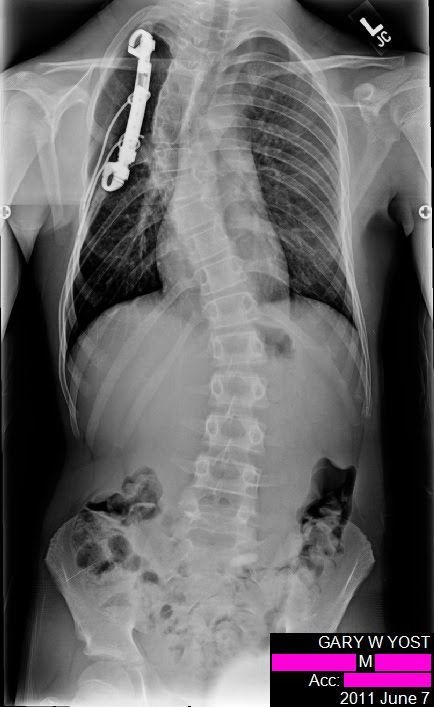

My life after treatment has been affected somewhat by physical problems with my prosthetics and generally missing multiple ribs. One of the things I did very quickly was break all of the wires in my back. Some of these segments were removed due to them painfully poking me. They have since stopped using wires with this style of reconstruction.

SpinalFusion.png

In freshman year of high school I was diagnosed with scoliosis, excessive spine curvature. I had approximately a (DEGREE) bend in my spine. The fix for this is a spinal fusion This is where metal rods are attached to the spine, and bone is packed into the surrounding area of the main vertebrae to allow the spine to grow its self into one chunk rather than individual articulating parts. Mine was from vertebrae ### - ###, this distance is relatively stiff in even "normal" people so this hasn't affected my range of motion to much.